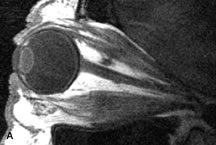

T2 RELAXATION TIME.

Application of a 90° RF pulse brings the excited nuclei into phase so that the net vector of their magnetic moments is directed perpendicular to the static magnetic field. Shortly thereafter, the magnetic moments of the nuclei spread out and point in different directions, leading to a loss of phase coherence and a resultant decay in signal intensity amplitude. The T2, or spin-spin relaxation time, is the rate of decrease in the signal of these excited nuclei as a result of the interaction and transfer of energy to unexcited adjacent nuclei. T2 ranges from a few milliseconds to a few hundred milliseconds and, for a given tissue, is always less than the Tl relaxation time. T2-weighted orbital images are easily recognized by a high-intensity signal from the vitreous (Fig. 9).5,8,16

Fig. 9. T2-weighted image of the orbits does not delineate normal anatomic details well. The lens can be visualized in the bright vitreous. (Dortzbach RK, Kronish JW, Gentry LR: Magnetic resonance imaging of the orbit. Part II. Clinical applications. Ophthal Plast Reconstr Surg 5:161, 1989)

T2-weighted pulse sequences are not ideal for imaging normal anatomy; however, they are particularly useful in revealing pathologic conditions (see Fig. 9). T2-weighted studies are most easily recognized by a bright vitreous signal.